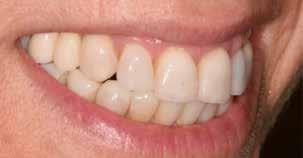

Hölgy páciensem az első konzultáció során tipikus kórtörténetet vázolt fel: Gyermekkora óta szeretett volna fogszabályozó készüléket, hiszen mindig is zavarta a class 2-es eltérésnél tipikusan jellemző nagy overjet (1-3. képek), és természetesen az ezáltal kifelé álló felső metszőfogai, részben a felső metszők protrúziója, részben pedig a disztálisan elhelyezkedő mandibula miatt. Annak ellenére, hogy több fogszabályozó szakorvosnál is járt az évek során, de mivel saggitális eltérése és az alsó metszőfogak torlódása miatt négy kisőrlőfog extrakcióját, illetve emellett sokszor állcsont műtétet is javasoltak neki, nem vágott bele a kezelésbe (4-5. képek).

A fogkontúrálás és az interproximális redukció alkalmazásával a mikroesztétikai részletek tökéletesítése is megtörtént (11. kép) A kezelés mindössze 16 hónapig tartott, megtörtént a rágófunkció helyreállítása, és az esztétikai végeredmény sokéves várakozás után valóban fordulópontot jelentett páciensünk életében (12-14. képek).